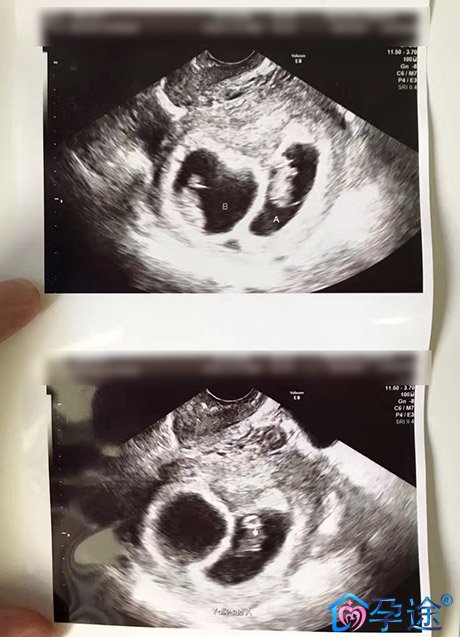

HCG确认怀孕,此阶段出血必须高度警惕宫外孕,需及时到医院就诊,尤其是HCG值偏低伴有腹痛的女性,因为宫外孕一旦发生腹腔内出血,可危及患者生命。如果B超显示宫内妊娠,则继续保胎治疗。

移植一个月后,移植术后B超确认宫内妊娠,此时出现少量出血,不必紧张,尽量卧床休息,保持心情平静,继续保胎治疗。